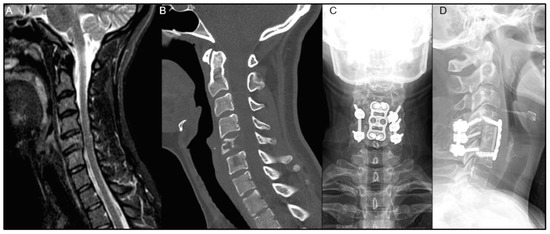

| Patient | Age/Sex | Primary Organ | Instrumented Levels | Radiation | Time to Wound Complication | Reoperation for Wound Complication |

|---|---|---|---|---|---|---|

| 1 | 58M | RCC | T10-L2 | Preop RT only | 48 days | No |

| 2 | 69M | Prostate ADK | T2-T9 | Preop RT only | 39 days | Yes |

| 3 | 44M | Lung ADK | T5-T9 | Postop EBRT | 14 days | Yes |

| 4 | 56F | Lung ADK | O-C5 | Postop EBRT | 22 days | Yes |

| 5 | 72M | Lung ADK | T1-T6 | Postop SBRT | 21 days | Yes |

| 6 | 52M | Lung ADK | C5-T5 | Postop EBRT | 22 days | Yes |